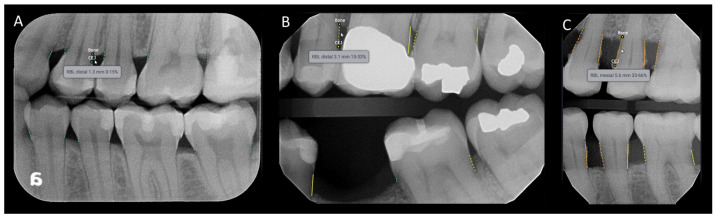

Figure 3.

Example of the Denti.AI software interface predicting radiographic alveolar bone loss for bitewing radiographs. The software detects and color codes the measurements: green for 0–15% (A), yellow for 15–33% (B), and orange for 33–66% (C). The measurements are displayed when the mouse is dragged over the area of interest.